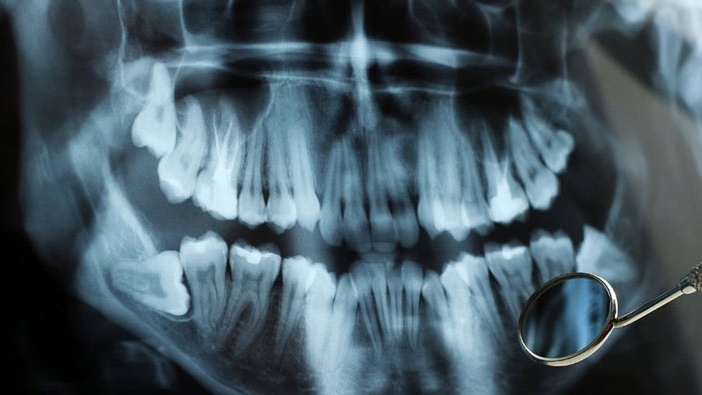

Để xác định vòng hàm có bị hẹp hay không, bác sĩ sẽ thăm khám trực tiếp và chụp X-quang để xác định. Chính vì vậy nếu xác định bạn có vòng hàm quá hẹp thì bác sĩ sẽ chỉ định kết hợp nong hàm để tạo sự cân đối cho khuôn mặt.